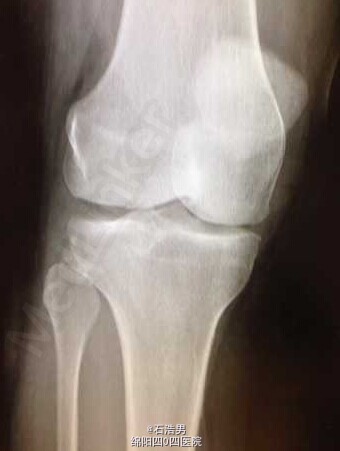

特殊断裂一例

患者,40岁,从7米高的梯子摔倒。此前并无任何受伤。我从来没有见过这个特殊的断裂,分享给大家